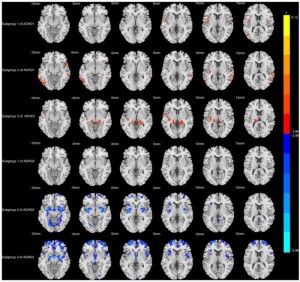

Scans: Unterschiede nachgewiesen (Foto: Tianzheng Zhong, Feng Wang, Jianfeng Qiu, Weizhao Lu) |

Mithilfe des maschinellen Lernens sind die Kinder mit ADHS, basierend auf ihrer Hirnstruktur, in Untergruppen aufgeteilt worden. Diese Analyse zeigt zwei klar abgegrenzte Untertypen. Jeder dieser verfügt bei den Veränderungen des Gehirns über eigene Muster und eigene Assoziationen mit dem Verhalten.

Der erste Untertyp steht vorwiegend mit Problemen mit der Aufmerksamkeit in Verbindung. Diese Kinder wiesen eine Zunahme des Volumens der grauen Substanz auf. Davon betroffen sind vor allem der Frontalkortex und das Kleinhirn.

Diese Areale spielen bei der Aufmerksamkeitskontrolle, dem Planen und der Koordination eine entscheidende Rolle. Werden die Symptome stärker ausgeprägt, werden auch diese Veränderungen offensichtlicher, so die Wissenschaftler.

Beim zweiten Untertyp weisen die Kinder eher eine umfassende Abnahme des Volumens der grauen Substanz auf. Das ist vor allem bei der Zunahme der Symptome der Fall. Am stärksten betroffen sind das Kleinhirn und der Hippocampus.

Diese Areale stehen mit der motorischen Kontrolle, der Emotionsregulation, dem Gedächtnis und der Motivation in Zusammenhang. Dieser Untertyp steht zudem mit der allgemeinen Schwere der Erkrankung in Verbindung.